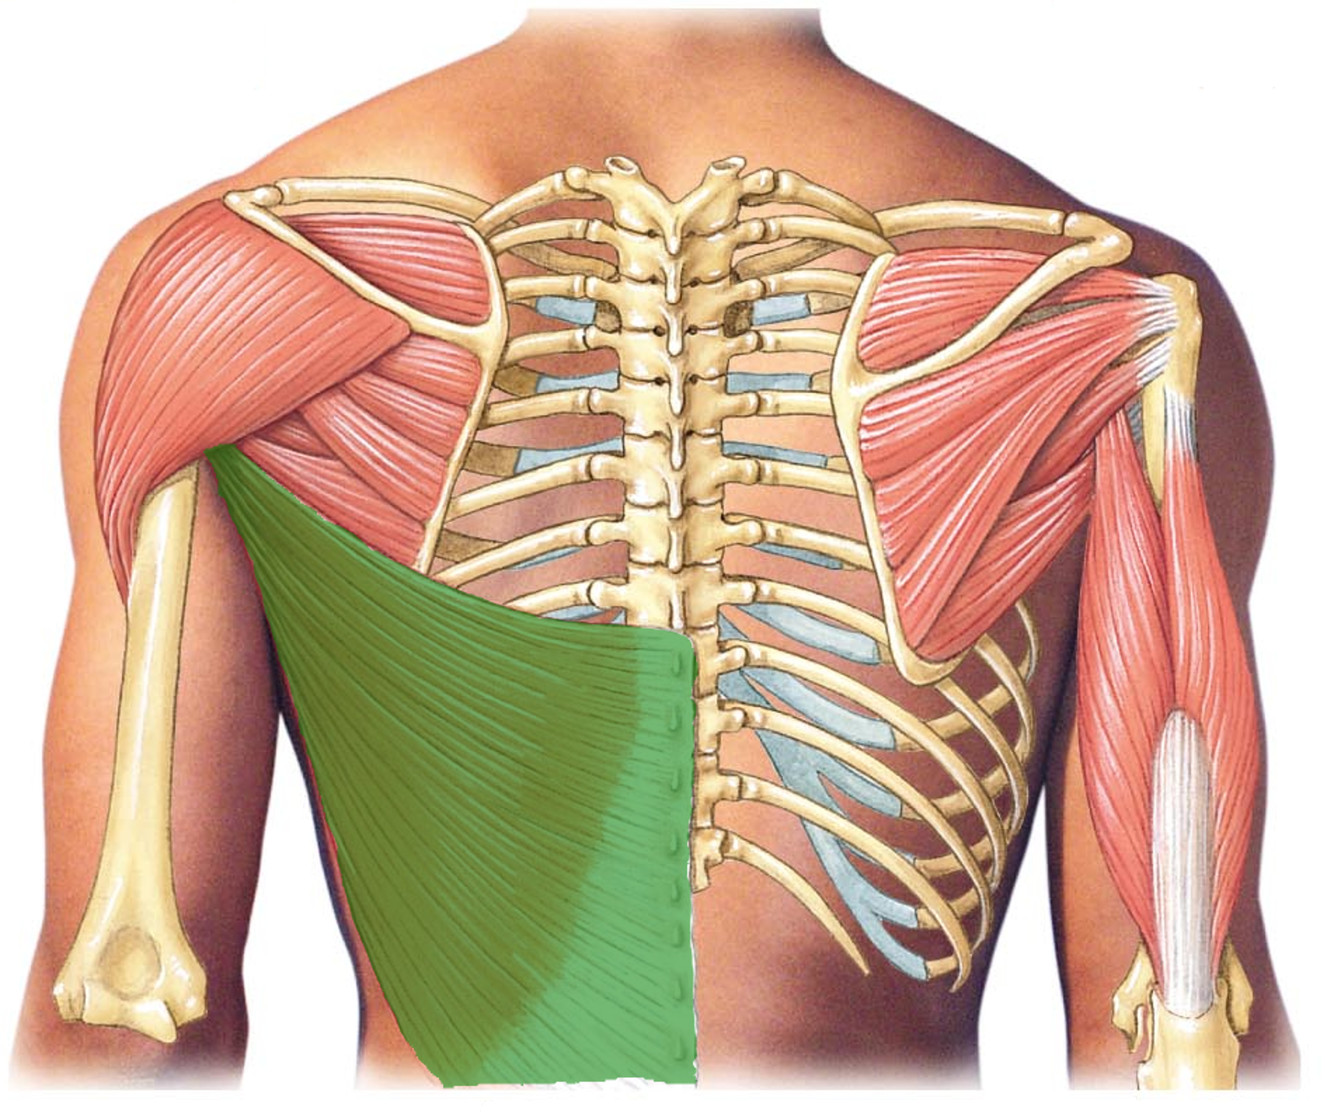

What is the innervation of this muscle?

Muscle - Subscapularis

Subscapular nerve C5-C7

What is the innervation of this muscle?

Muscle - Latissimus dorsi

Thoracodorsal nerve

C6-C8